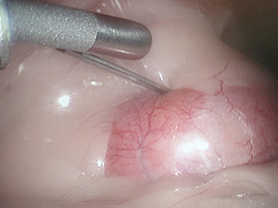

お腹の中を見ながら目的の腎臓の近くに生検用の針を刺します。

腎臓に針を刺して組織を採取します。

生検した腎臓の組織です。